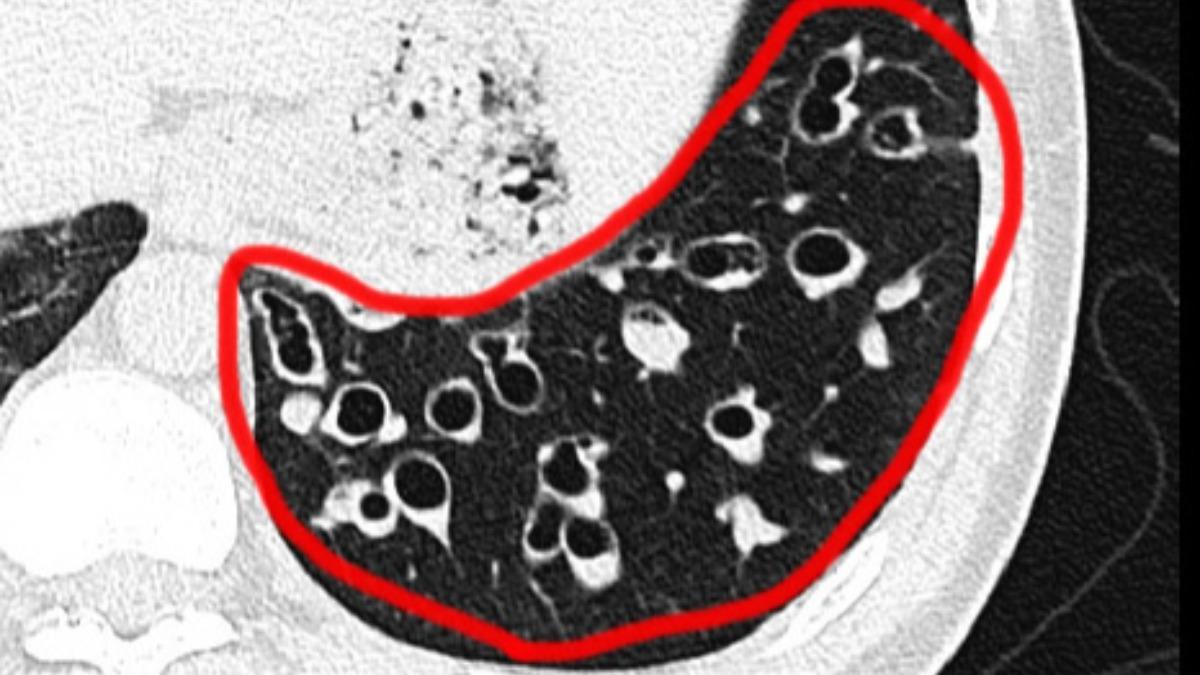

據了解,甘男年僅30歲,就長期受支氣管擴張症困擾,且因痰液大量堆積,每2到3分鐘就得咳痰,甘男也補充,「每天起床不能賴床,第一件事就是拼命把痰排出,否則會被噎死」,後續前往台中榮總求診後,確診為雙下肺支氣管擴張症合併嚴重痰液阻塞。